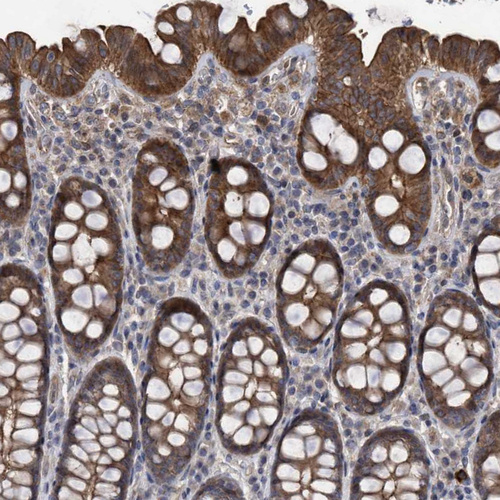

Immunohistochemistry analysis in human parathyroid gland and smooth muscle tissues using Anti-COBL antibody. Corresponding COBL RNA-seq data are presented for the same tissues.